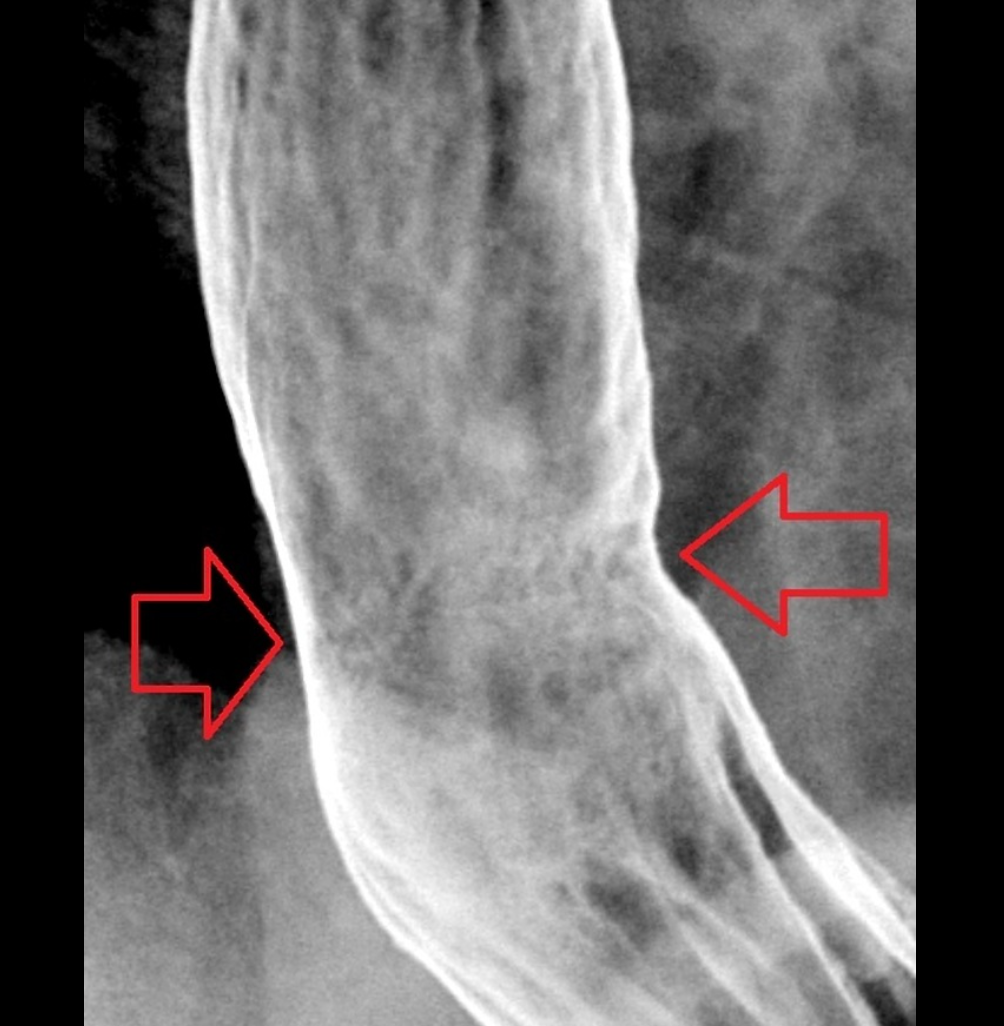

WHAT IS THIS?

histopathology

- Oesophagus is abnormally lined with columnar, metaplastic acid-secreting gastric mucosa.

- It is usually due to chronic reflux oesophagitis.

- Because there is an increased risk of oesophageal cancer, close follow-up and repeated biopsies are recommended

- IMAGING FEATURES

- A reticular mucosal pattern which may be discontinuous in the distal oesophagus (short segment) is the most sensitive finding.

- Suspect diagnosis if there is

- upper or midoesophageal stricture accompanied by reticular mucosal pattern below transition or ulcer

- Low strictures:

- the majority cannot be differentiated from simple reflux oesophagitis strictures and biopsies are required.

https://radiopaedia.org/cases/barrett-oesophagus?lang=gb

Zoomed-in images of the fine reticular pattern superimposed on oesophagitis (fine granular pattern) found in Barrett oesophagus. The area of fine reticulation is either circled in red or pointed to with red arrows.

Thanks to Steve Rubesin MD for this case.

Case Discussion

Biopsy proven Barrett oesophagus (no histologic dysplasia). This is more than an incidental finding on an oesophagram – this is a critical finding. By the time you find a lobulated oesophageal carcinoma it’s too late; the patient needs to be treated and followed at the first signs of metaplasia in the normal oesophageal stratified squamous epithelium.

It is important to get enough air/gas in the oesophagus in order to optimise one’s double contrast technique and pick up subtle findings like this. In addition to effervescent granules, it is often helpful to tell the patient to swallow as much air as possible while drinking the barium.

In this example, the Barrett oesophagus is at the gastro-oesophageal junction, but it can occur in patches anywhere from the mid-oesophagus down to the gastro-oesophageal junction.